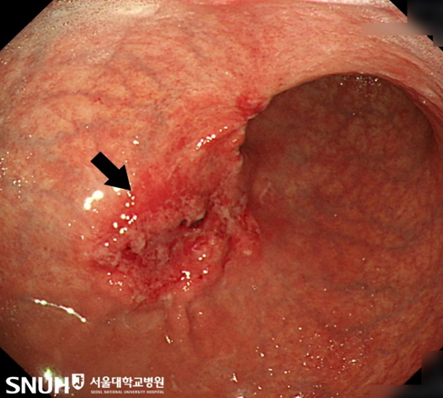

[Снимок] Рак желудка на гастроскопии |

Самый важный способ диагностики рака желудка – гастроскопия. Существует также рентгеноскопическое исследование желудка, однако этот способ диагностики практически не может выявлять рак желудка на начальных стадиях. Гастроскопия – самый эффективный способ диагностики рака желудка, при котором проверяются стенки желудка и при обнаружении подозрительных участков делается биопсия.